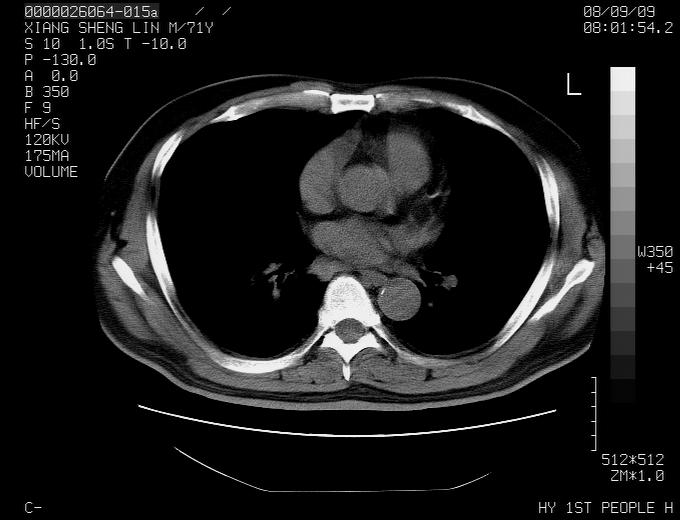

标题: CT15869:男性,71岁,因咳嗽而就诊,请讨论右上肺病变性质 [打印本页]

标题: CT15869:男性,71岁,因咳嗽而就诊,请讨论右上肺病变性质

患者,男性,71岁,因咳嗽而就诊,

典型的右肺中心性肺癌并纵隔淋巴结转移

考虑右肺中心性肺癌并右肺门及纵隔淋巴结转移。

1,右肺中心型ca,气管隆突旁淋巴结转移。

2,右膈明显抬高,建议肝脏扫描排除转移或原发灶。